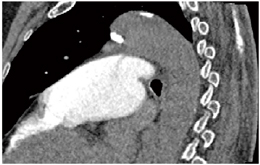

volume rendering(VR)の4Dでは,造影剤が左心室から大動脈に流れていく状態と,PDAの位置を任意の角度から確認することができる(図3)。また,multiplanar reconstruction(MPR)の4Dでは,VRでは確認できない任意の断面の状態や,肺動脈へのジェットの状態を確認することができる(図4)。また,MPRでは,PDAの径を計測することも可能である(図5)。

![]() 図4 PDA症例のMPR像 |